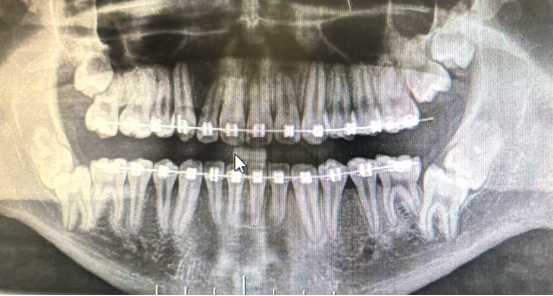

当然,很多时候仅凭肉眼是无法判断自己的智齿生长状态,所以一定要去看牙医,拍了牙片才能知道自己的智齿“千奇百怪”。